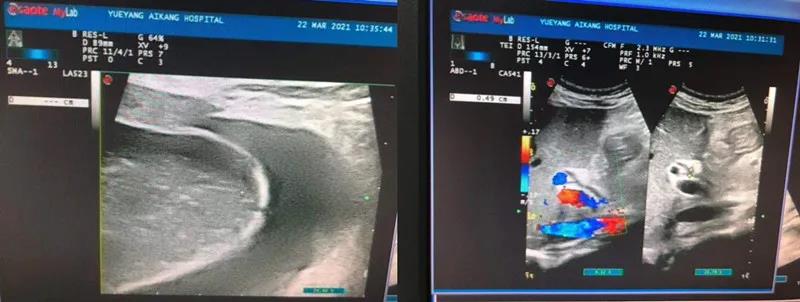

彩超檢查結(jié)果顯示:膽囊腫大、膽囊結(jié)石、急性膽囊炎

劉主任得知檢查結(jié)果后,迅速請(qǐng)普外科醫(yī)生會(huì)診。普外科周旭陽(yáng)主任看到彩超結(jié)果單,提出需盡快手術(shù),否則隨時(shí)有穿孔的危險(xiǎn)。而劉主任則擔(dān)心手術(shù)會(huì)發(fā)生產(chǎn)褥期感染,影響產(chǎn)后恢復(fù)。然而周主任的診療方案很快消除了劉主任的擔(dān)憂,張女士被迅速轉(zhuǎn)入普外科。